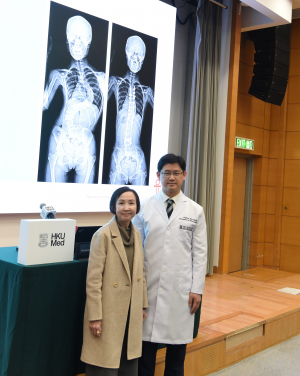

港大醫學院發現青少年原發性脊柱側彎患者的遺傳成因

由香港大學李嘉誠醫學院(港大醫學院)臨床醫學學院矯形及創傷外科學系鍾培言教授和生物醫學學院宋又強博士,以及香港中文大學醫學院生物醫學學院高波博士領導的跨學科研究團隊,近日取得全球性突破,成功識別青少年原發性脊柱側彎(Adolescent Idiopathic Scoliosis,AIS)的主要成因。AIS是最常見的脊柱畸形,影響全球數以百萬青少年。團隊發現SLC6A9基因變異,令突觸神經傳送及中樞模式發生器 (Central Pattern Generators)失調,導致脊柱側彎;這項重大發現已在學術期刊 《臨床研究期刊》 (The Journal of Clinical Investigation)發表(按此瀏覽期刊文章)。

由於醫學界對AIS的病因仍未有共識,因而阻礙了早期干預。目前已知遺傳因素對誘發AIS起著重要作用,惟此病的遺傳成因和病理機制至今仍然未明。港大醫學院臨床醫學學院矯形及創傷外科學系主任兼臨床教授鍾培言教授表示:「我們的研究旨在識別與AIS相關的基因變異,填補對遺傳成因與AIS關係方面知識的不足,開創為AIS患者提供針對性和個人化的治療新方案。」

這項突破性硏究不但揭示導致AIS的遺傳因素,更為研發新的診斷方法和預防療法創造條件。鍾教授補充:「我們可通過進一步研究和臨床試驗,革新目前對AIS的治療策略,希望能大大改善AIS患者的生活。」

研究團隊由港大醫學院臨床醫學學院矯形及創傷外科學系主任兼臨床教授鍾培言教授、港大醫學院生物醫學學院首席講師宋又強博士及香港中文大學生物醫學學院副教授高波博士領導。第一作者包括港大醫學院臨床醫學學院矯形及創傷外科學系王小魯及港大醫學院生物醫學學院岳明。團隊成員包括港大醫學院臨床醫學學院矯形及創傷外科學系張頴恒醫生、王小軍、胡勇博士、陸瓞驥教授;港大醫學院生物醫學學院范彦輝、吳美澄、陳喆溢及陳振勝教授;港大醫學院臨床醫學學院兒童及青少年科學系涂文偉教授及王系偉博士;以及北京協和醫院、德州Scottish Rite Hospital for Children、中國科學院香港創新研究院再生醫學與健康創新中心及日本理化學研究所。